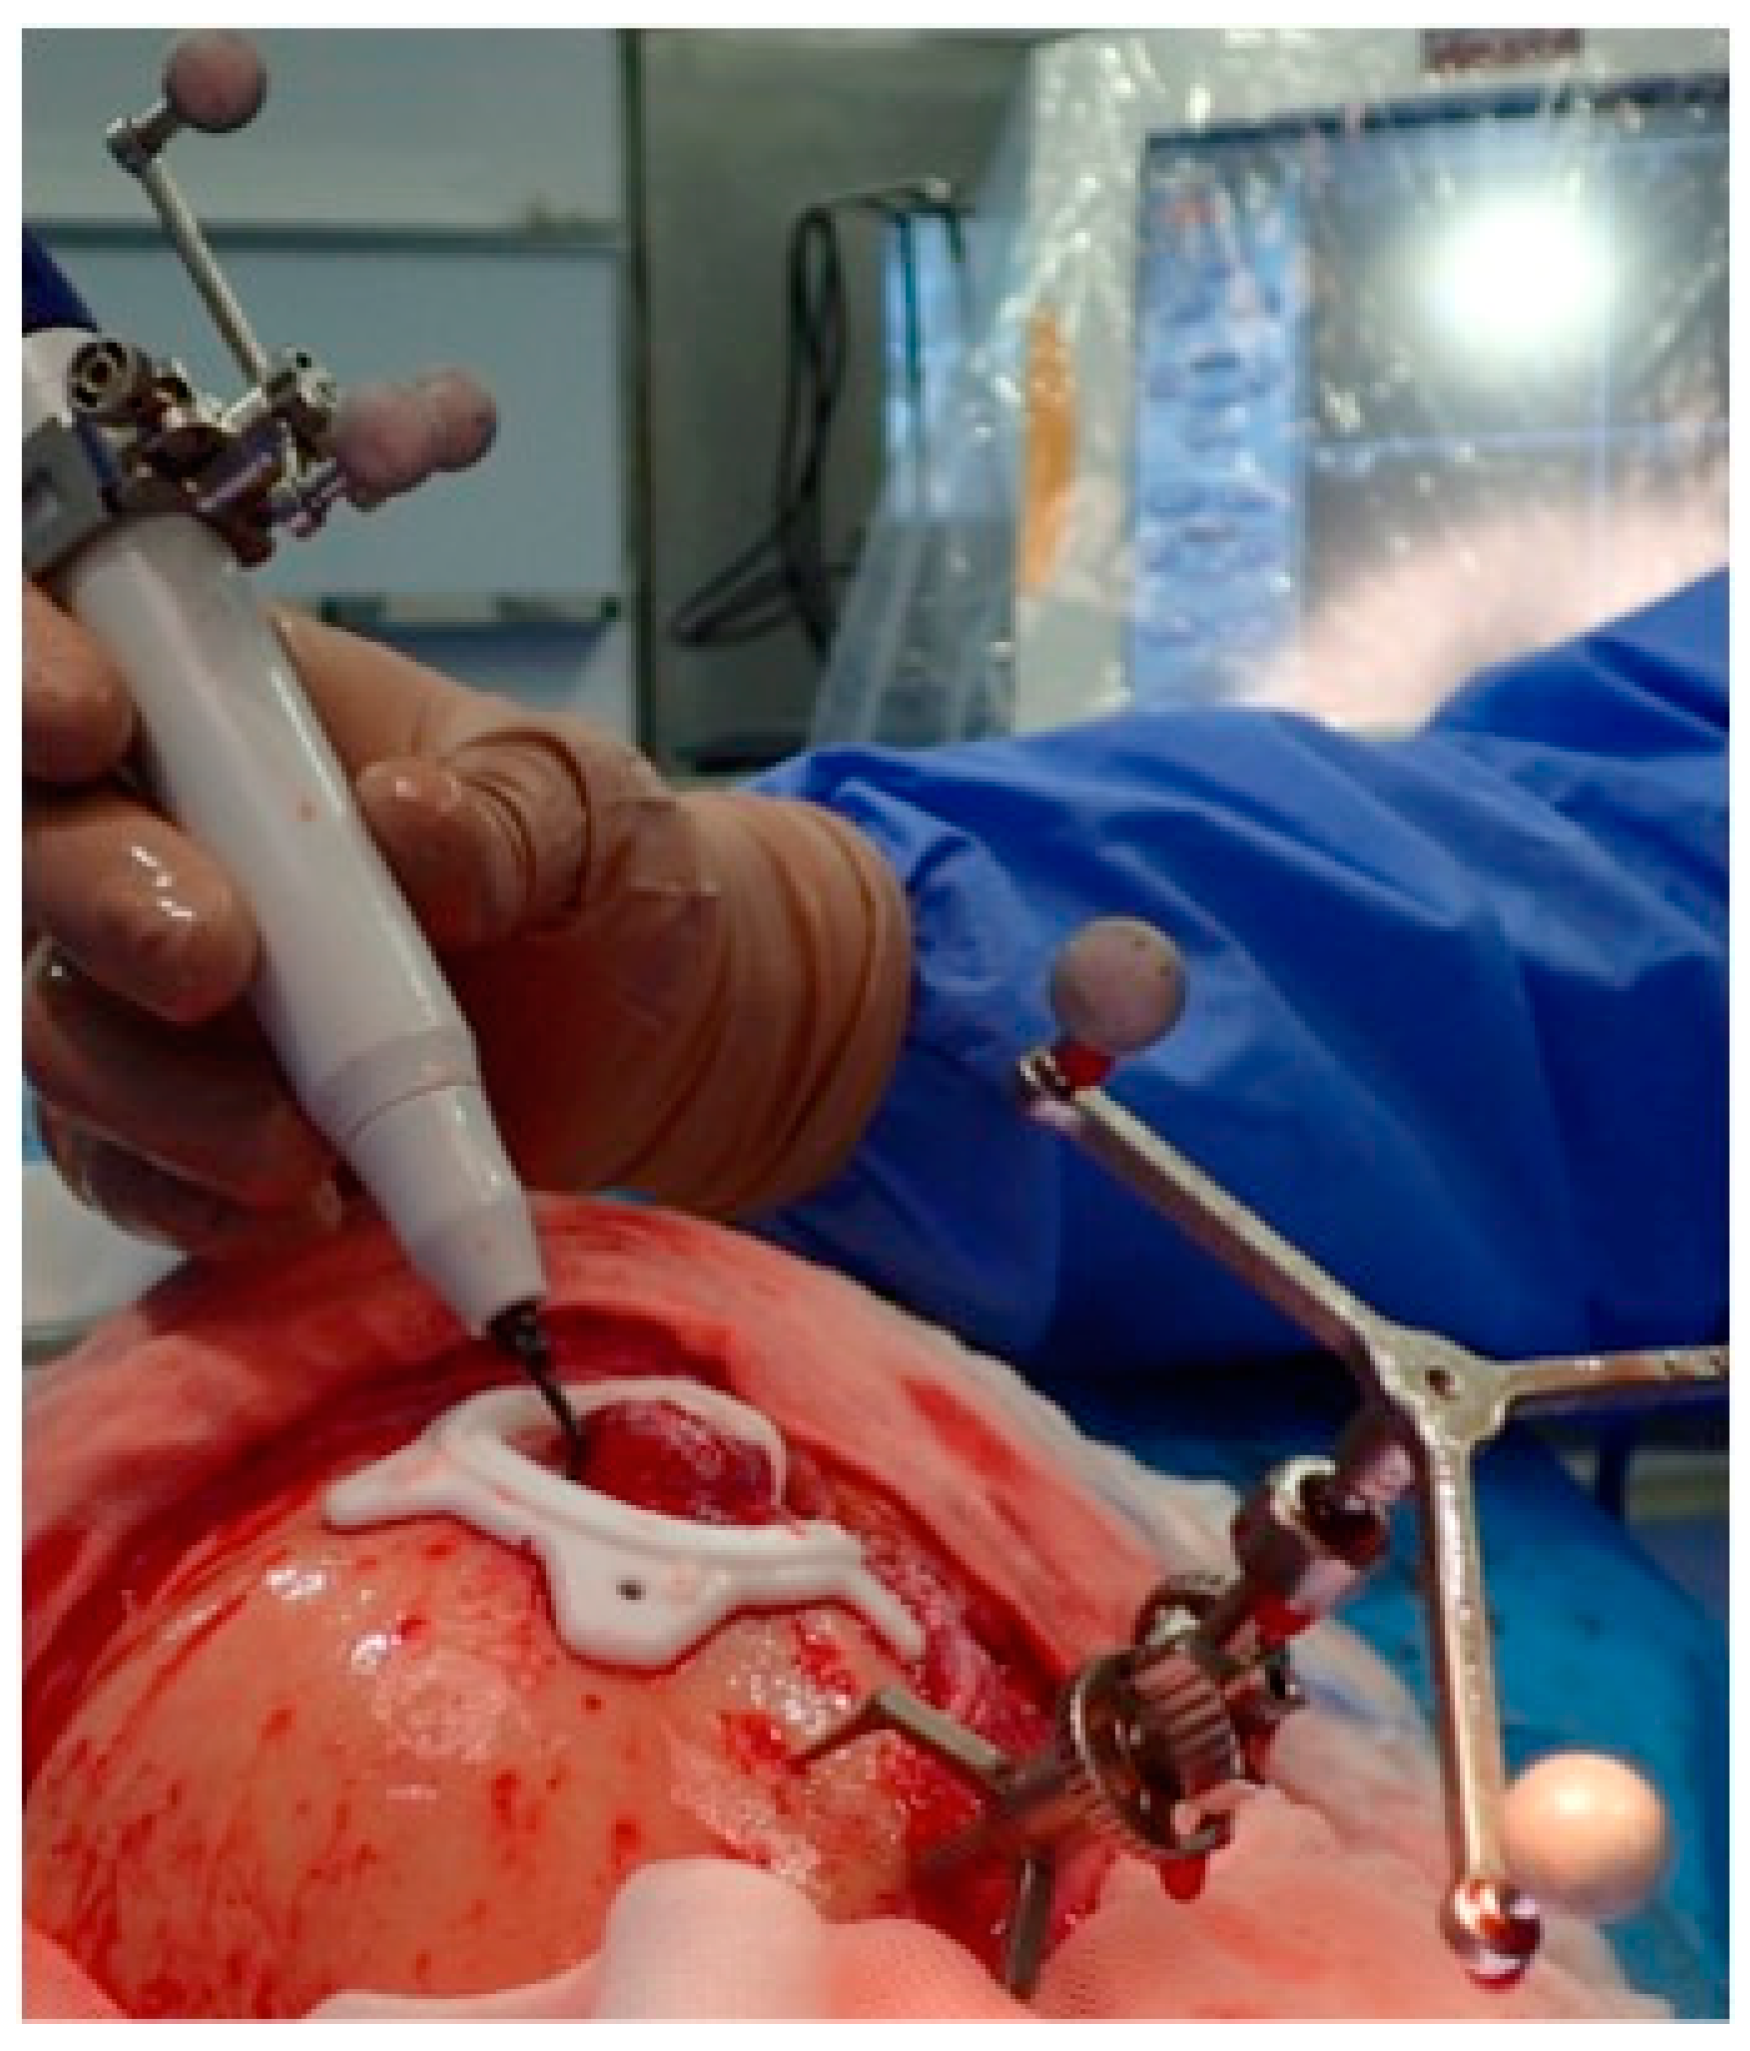

2.3.3. Surgical Navigation

- Bianchi, A.; Badiali, G.; Piersanti, L.; Marchetti, C. Computer-Assisted Piezoelectric Surgery: A navigated approach toward performance of craniomaxillofacial osteotomies. J. Craniofac. Surg. 2015, 26, 867–872. [Google Scholar] [CrossRef]

- Dean, A.; Heredero, S.; Solivera, J.; Sanjuan, A.; Alamillos, F.J. Computer-assisted and navigated piezoelectric surgery: A new technology to improve precision and surgical safety in craniomaxillofacial surgery. Laryngoscope Investig. Otolaryngol. 2022, 7, 684–691. [Google Scholar] [CrossRef]